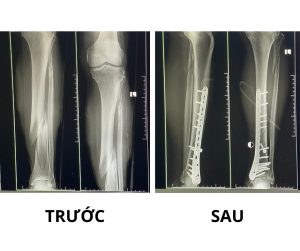

Bệnh nhân T.M.H (65 tuổi) sau TNGT được đưa đến Bệnh viện Đa khoa Bố Hạ trong tình trạng sưng nề, đau, không vận động được chân trái.

Bệnh nhân được sơ cứu ban đầu, khám lâm sàng kết hợp kiểm tra đánh giá tổng thể, trong đó chụp X-quang phát hiện gẫy kín 1/3 dưới xương chày và 1/3 trên xương mác trái. Được chỉ định phẫu thuật kết hợp xương 1/3 dưới xương chày trái.

Sau khoảng 02 giờ xử lý tổn thương, ca phẫu thuật kết thúc an toàn, xương gãy được cố định vững chắc. Hiện tại, tình trạng bệnh nhân đã ổn định và có dấu hiệu phục hồi tốt.